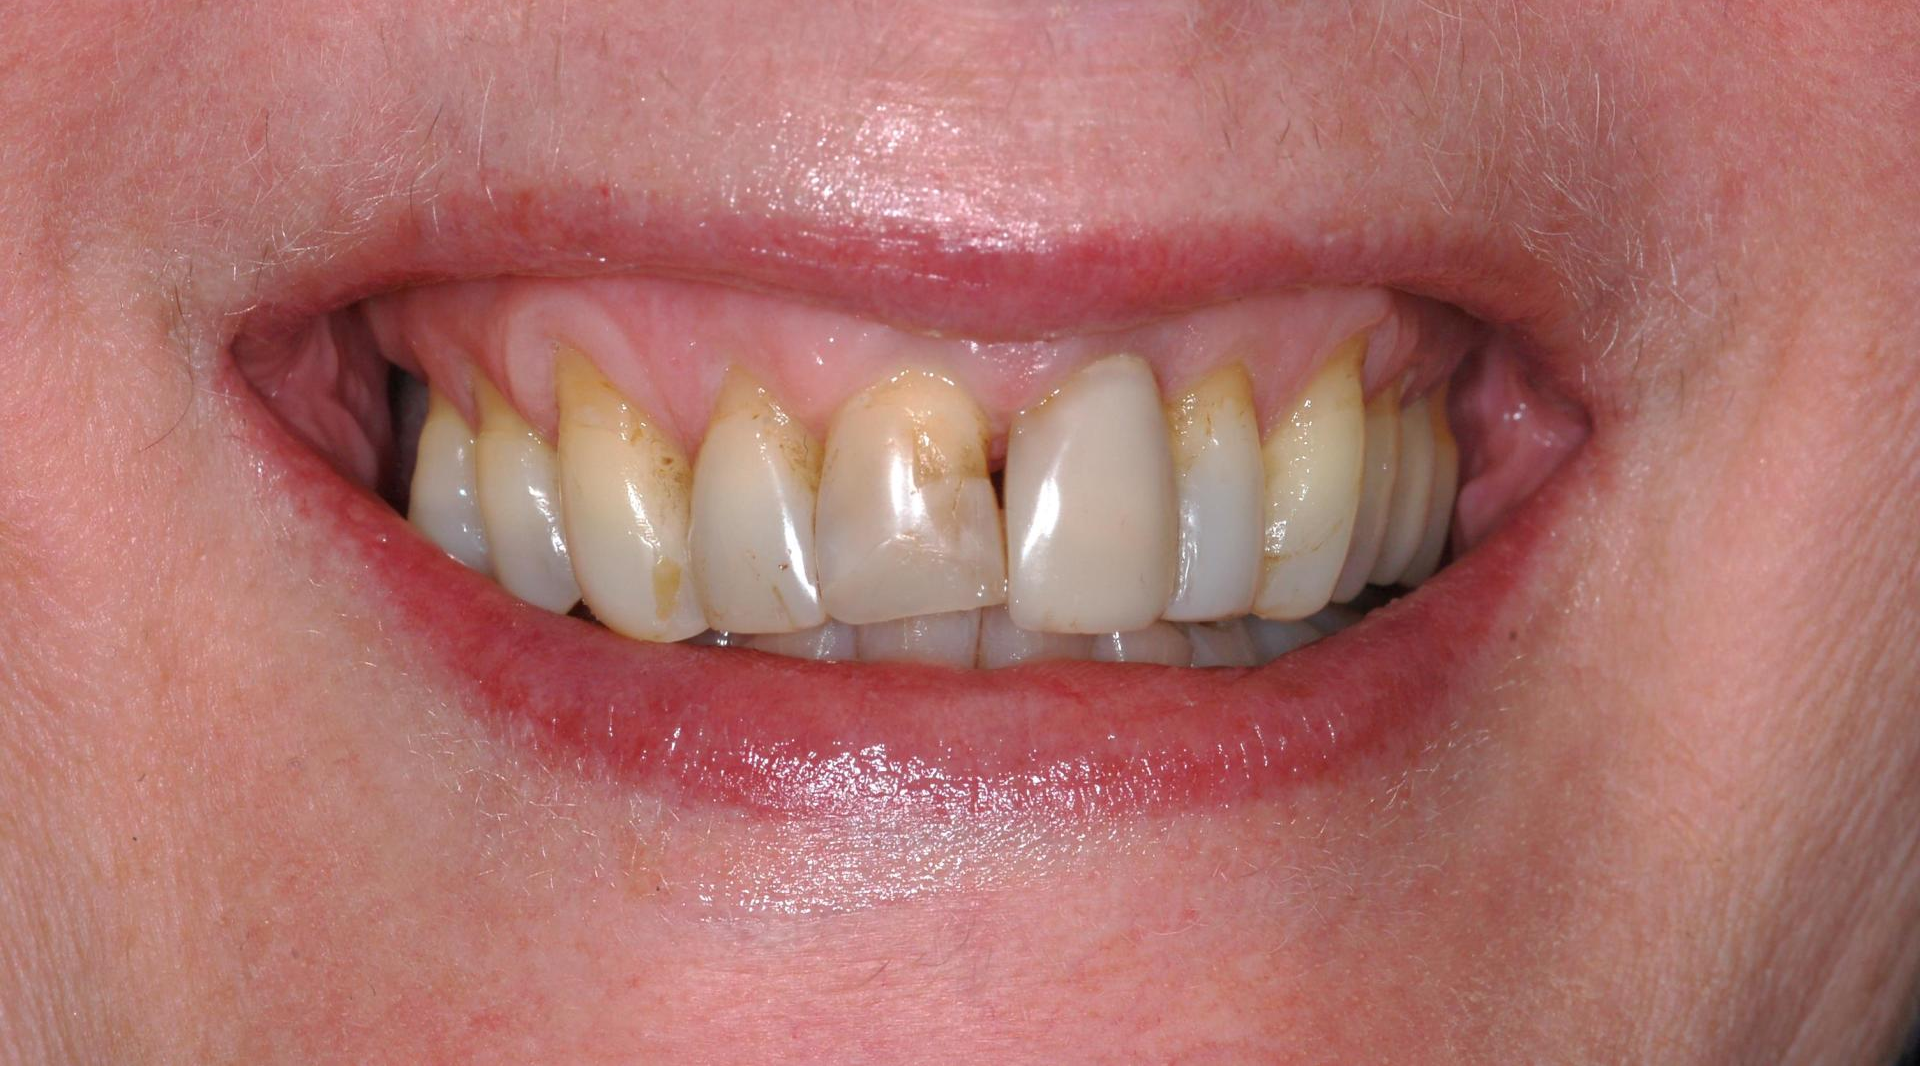

Porcelain Crowns

This patient was unhappy with the short length and discolouration of her teeth. We did a wax up study to evaluate the ideal size and length for her teeth. We then proceeded with six anterior porcelain crowns.